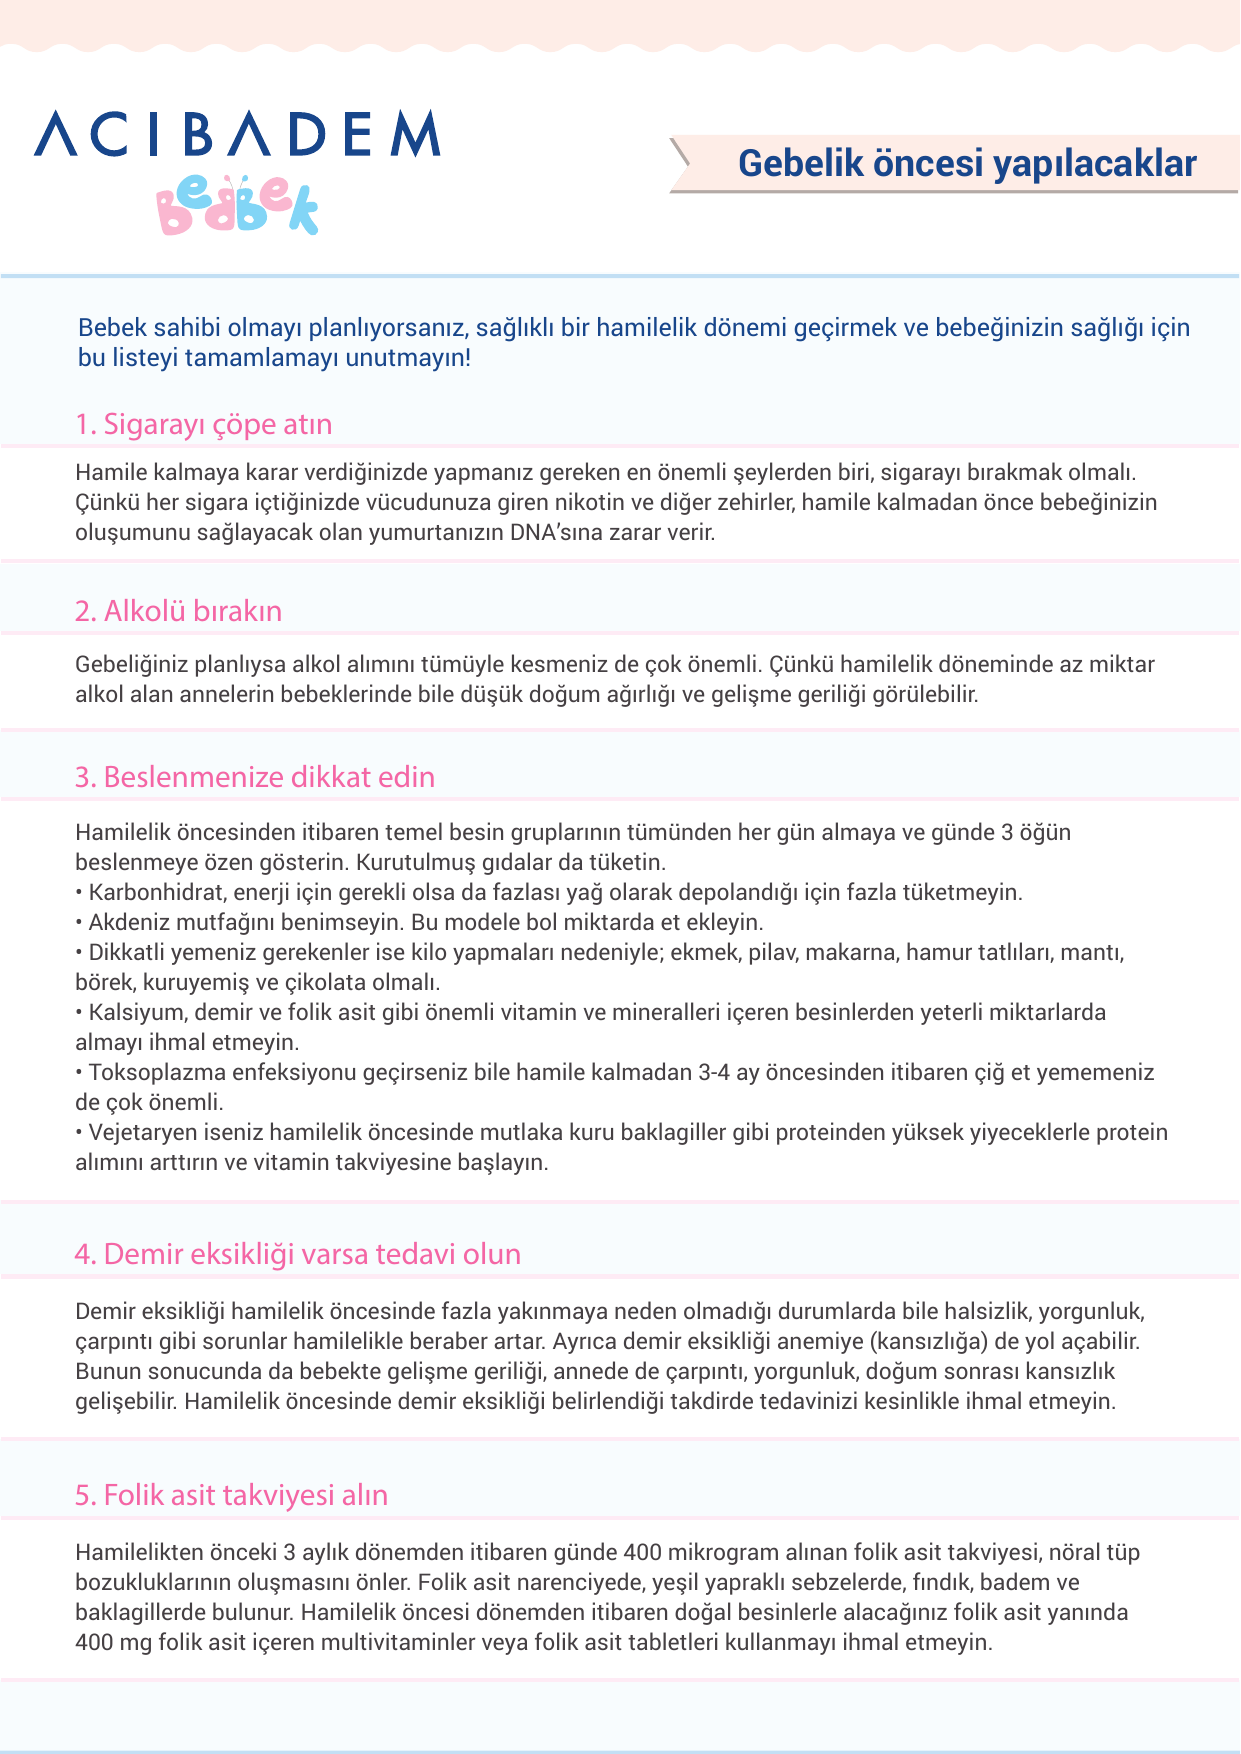

Hamile kalmadan önce. Hamile kalmayı planlıyorsanız hamilelikten önce diş doktoruna gitmelisiniz. Blog yazılarımızda beslenme ve fitness gibi ya da bebeğimizden sütten kesim sonrası beslenme ilgili ipuçlarına kadar her şeyi konu alıyoruz. çünkü hamilelik döneminde az miktar alkol alan annelerin. Hemen 400 mcgr folik aside başlayın.

Hamile kalmadan önce hangi testleri yaptırmalısın. Kan uyuşmazlığı durumunda hamile kalırsan ne olur. Yani hem siz hem de eşiniz sağlıklı beslenmeye başladığınızda hamile kalma olasılığınız daha yüksektir. Hem gebe kalmadan önce hem de hamilelik boyunca haftada 5 gün en az 30 dakikalık tempolu egzersiz yapmak genel sağlığınız açısından önemlidir.

Bu yazımızda hamile kalmaya çalışırken neler tüketmeniz. Bu hastalığın yaşanma sıklığı düşük. Günlük alınan alkol miktarı fazla olduğunda ise bebeklerde. çünkü hamilelik döneminde az miktar alkol alan annelerin bebeklerinde yeterli kiloya ulaşamama ve gelişme geriliği gibi sağlık sorunları görülebilir.

Hamile kalmadan önce en geç siklusun ikinci yarısında alkol alımını tümüyle kesmeniz de çok önemli. Hamile kalmadan önce bir diğer dikkat edilmesi gereken konu ise alkol alımının tümüyle kesilmesi gerektiğidir.